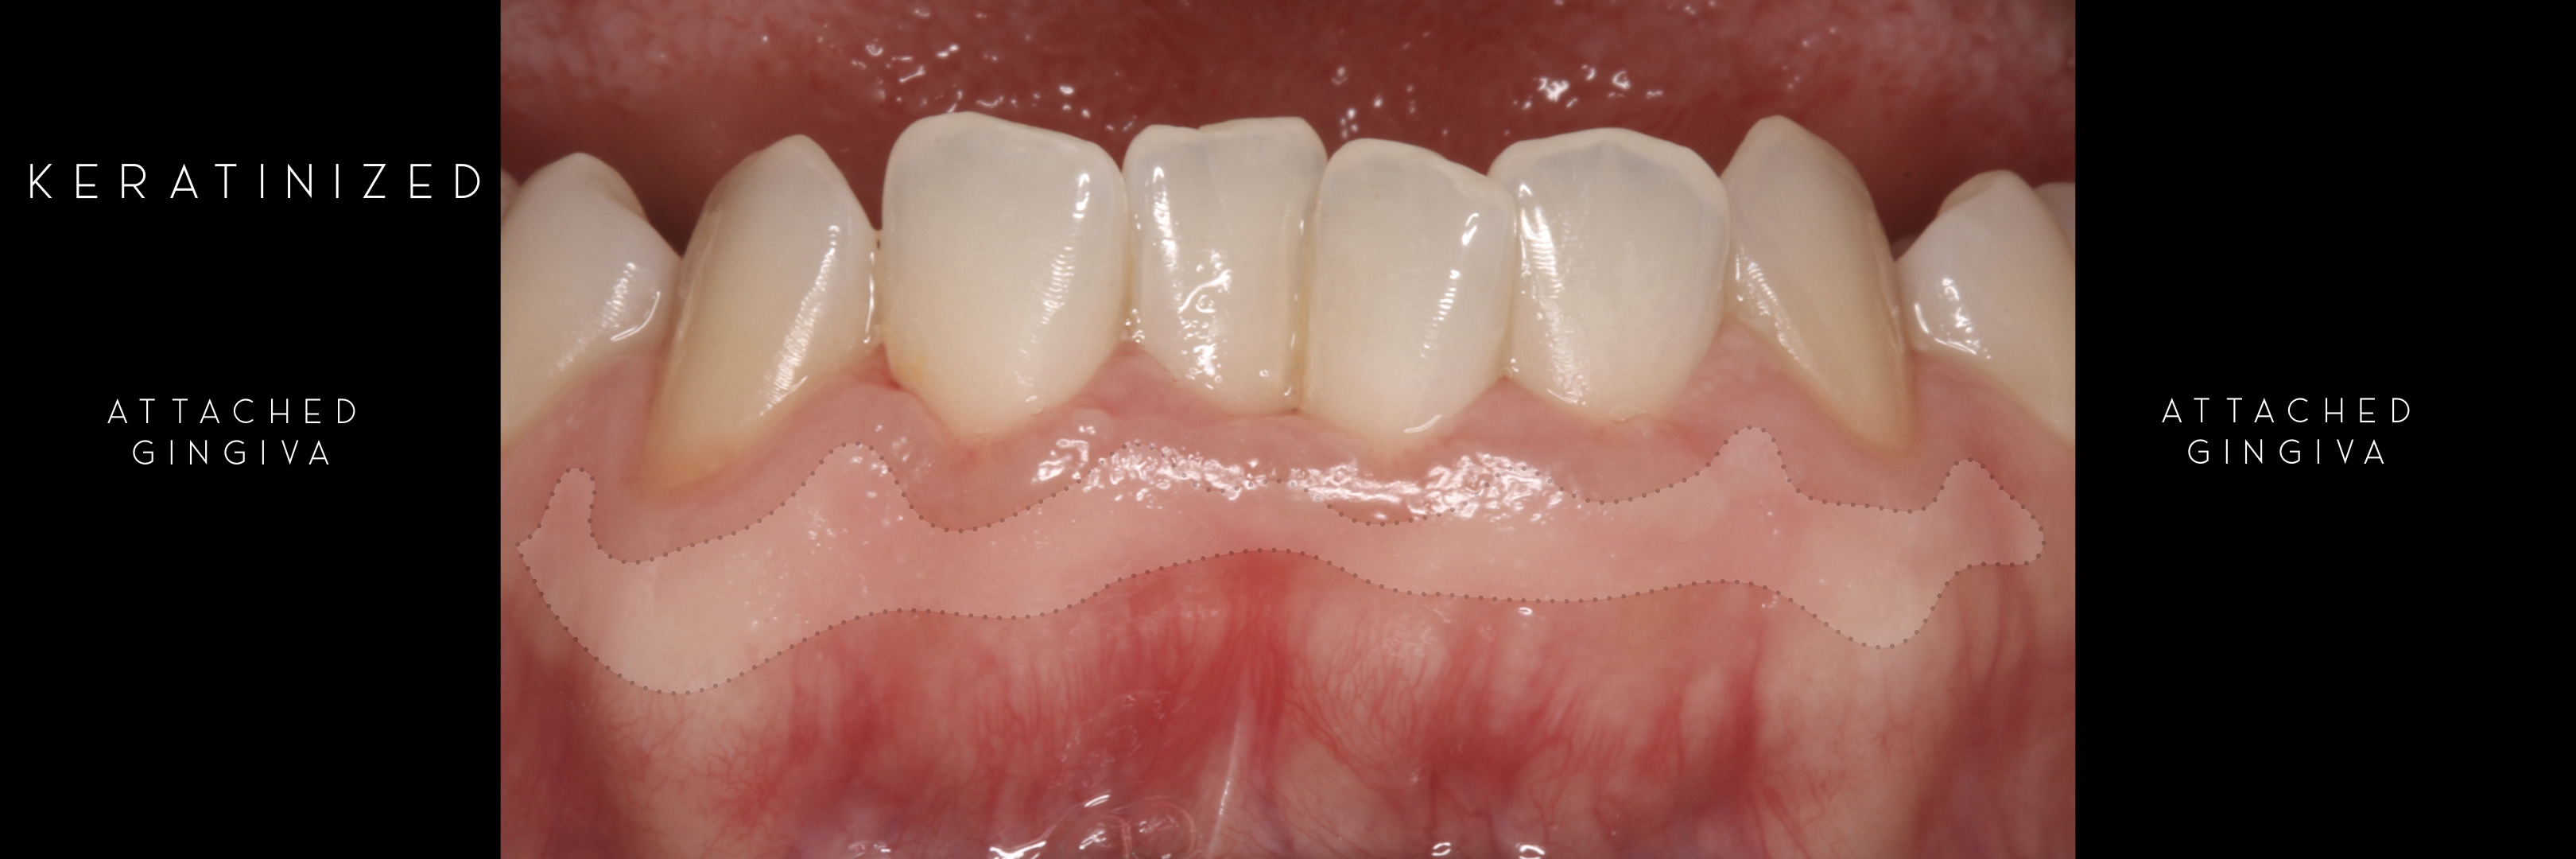

KERATINIZED gingiva includes

the free gingiva

(marginal gingiva & papillae)

and the attached gingiva extending from the gingival mar­gin to the mucogingival junction.

Generally we tend to forget about these 2 parameters, free and the attached gingiva are both essential parts of the keratinized gingiva.

This meaning that keratinized (load bearing capacity) is a mechanical characteristic that makes up for attached gingiva, providing it's immobility,  but also is of such importance as the thickness it provides around whatever perforates the epithelium, be it implants or teeth, being also keratinized (having load bearing capacity) at this location.

The width of the keratinized gingiva may vary between 1 and 9mm.

However, the question of how much gingiva is "adequate" has still not been investigated.

There was no answer at the time of Lang and Löe's paper -1972 - and still nowadays we still lack a final answer, but attached gingiva plays a major role on stable soft tissues around teeth and implants.